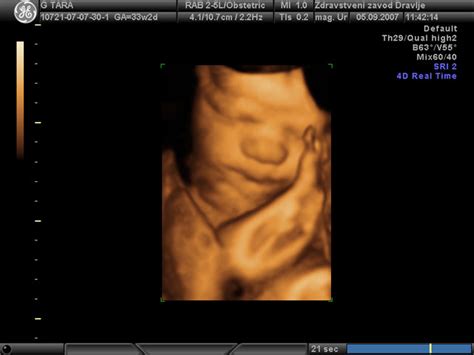

Poleg OBMP, ZC Dravlje nudi tudi celovito ginekološko oskrbo, vključno s pregledi v nosečnosti in vodenjem nosečnosti. Ekipa ima dolgoletne izkušnje na tem področju. Uporabljajo najnovejšo ultrazvočno in drugo tehnologijo, ki omogoča spremljanje rasti in razvoja ploda ter razjasnitev najrazličnejših težav v nosečnosti. Ultrazvok je varna in enostavna metoda, ki nudi vpogled v notranjost maternice, omogoča opazovanje ploda v 2D tehniki (statične slike ali film).